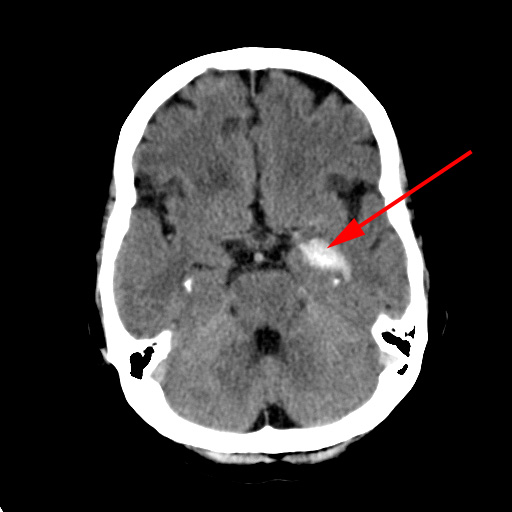

CT-skanning af cerebrum der viser en frisk blødning i hjernen (rød pil) hos to forskellige patienter.